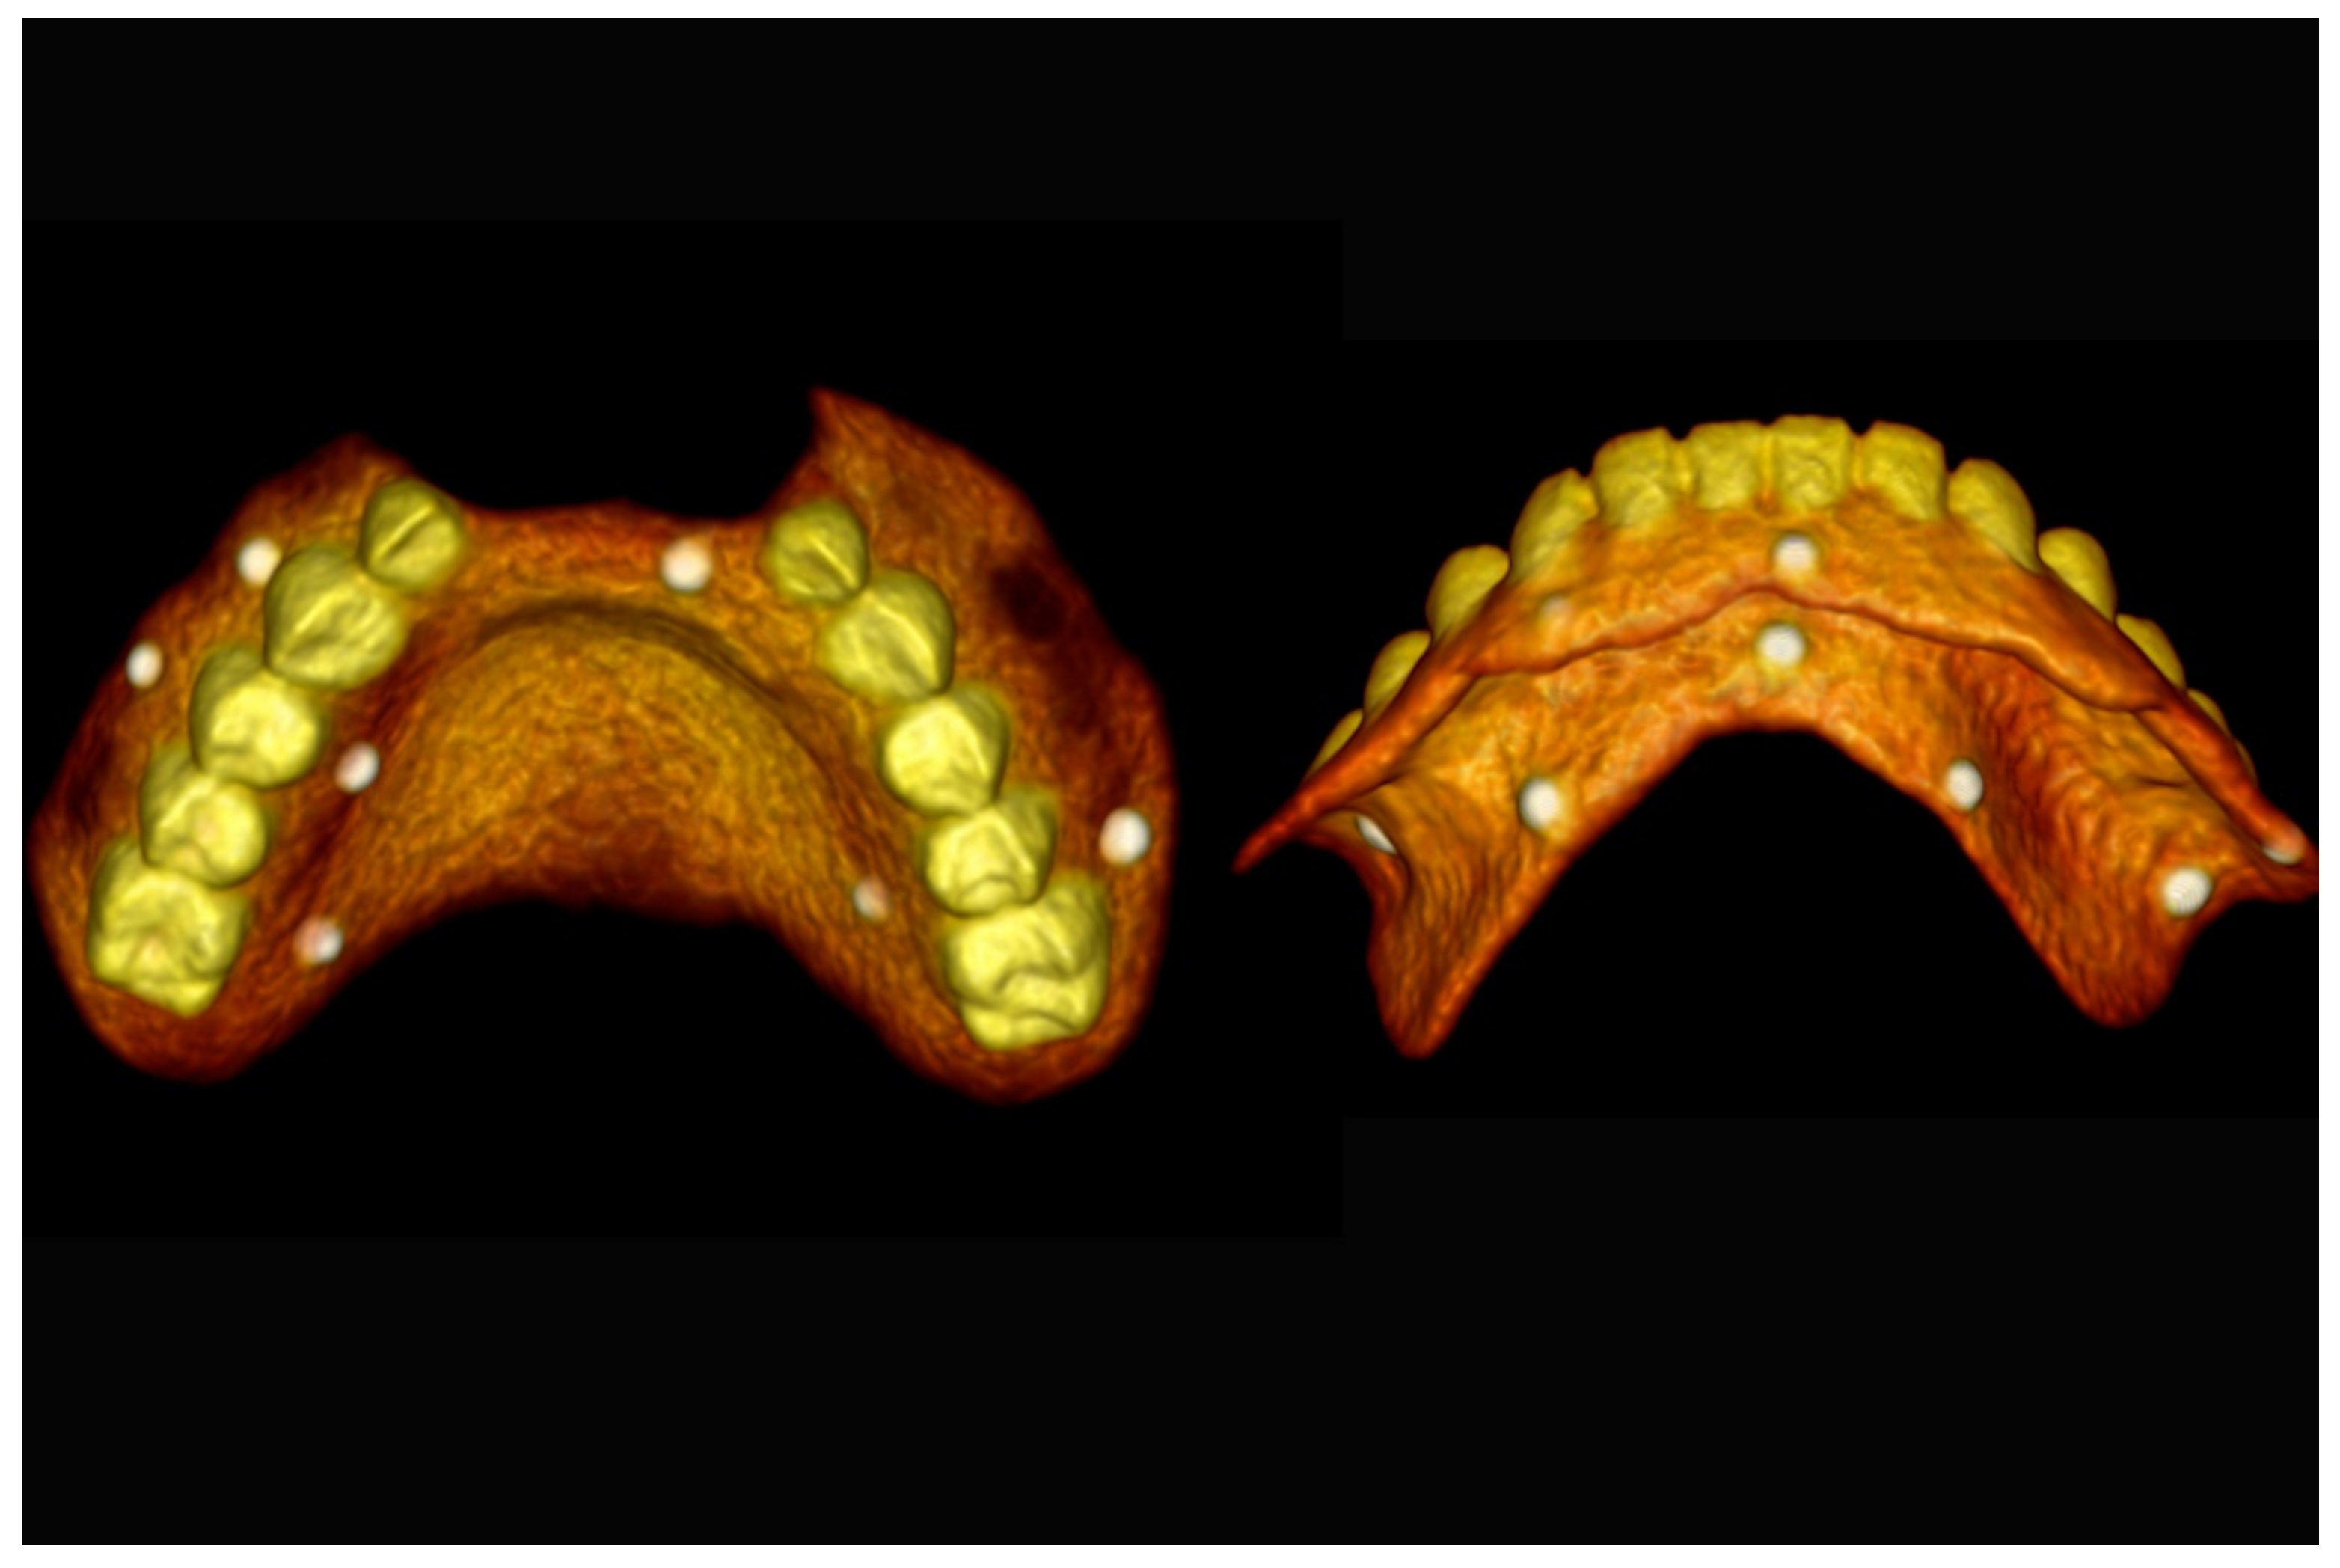

6.2.2. Preoperative Documentation

6.3.2. Preoperative Documentation: